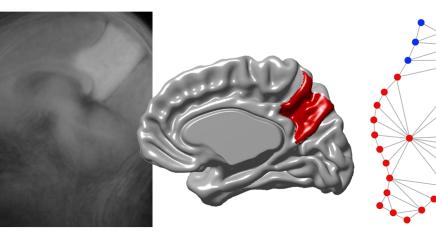

Otro estudio cuyo primer autor también es Emiliano Bruner, publicado recientemente en la portada de la revista Journal of Anatomy, ha analizado cómo cambia el precúneo durante el envejecimiento normal y cuando concurre la enfermedad de Alzheimer. Se compararon 39 cerebros de personas con alzhéimer, confirmados post mortem, procedentes del Banco de Tejidos BT-CIEN, con un grupo de control formado por 42 cerebros de personas mayores sin deterioro cognitivo del Proyecto Vallecas, a las que se había hecho un seguimiento durante una década.

En otro estudio se detalla cómo varía la forma y organización anatómica de esta región con la enfermedad de Alzheimer

El trabajo mostró que en el envejecimiento normal la zona superior del precúneo tiende a mostrar surcos más abiertos por la pérdida de tejido, mientras que la zona inferior reduce progresivamente su tamaño. En individuos con enfermedad de Alzheimer, esta reducción es más pronunciada, y esta región inferior se ve progresivamente invadida por los tejidos cerebrales contiguos.

Aunque se sabía que el precúneo es una de las áreas más vulnerables en las fases tempranas del Alzheimer, este trabajo describe por primera vez con detalle cómo varía su forma y organización anatómica en comparación con el envejecimiento normal, lo que ayuda a entender por qué la expansión evolutiva de esta región en nuestra especie es especialmente sensible a la neurodegeneración.

Cerebral Cortex 2025 / Bruner and Gallareto-Sande